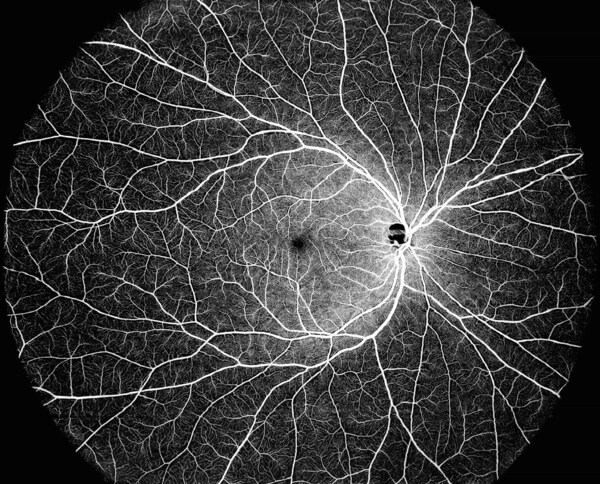

DREAM OCT는 초광각 단일 스캔을 통해 한 번에 130° OCTA 이미지를 제공할 수 있다. DREAM OCT™의 스웹트 소스(swept-source) 기반 12mm 초심도 스캔은 맥락막(choroid)과 망막(retina) 및 유리체 공간의 넓은 영역까지 선명하게 촬영할 수 있게 해준다. 초심도 전안부 스캔 기능은 공기 상에서 16.2mm까지 스캔이 가능해 각막(cornea)부터 유리체(vitreous) 전방까지 전안부 전체를 단 한 번의 스캔으로 완전히 스캔 가능하다. 더 길어진 파장은 수정체나 유리체 내 혼탁한 부분의 우수한 통과를 지원한다.

초광각 스웹트 소스 기술을 활용하는 DREAM OCT는 향상된 치료와 결과를 위해 고해상도 이미징 기능을 통해 망막 전문의와 종합 안과 의사뿐 아니라 그들이 돌보는 환자의 요구사항을 충족시키기 위해 개발됐다. 현재까지 160편 이상의 동료 검토를 끝낸 논문이 DREAM OCT 기기에서 얻은 결과를 활용했다.